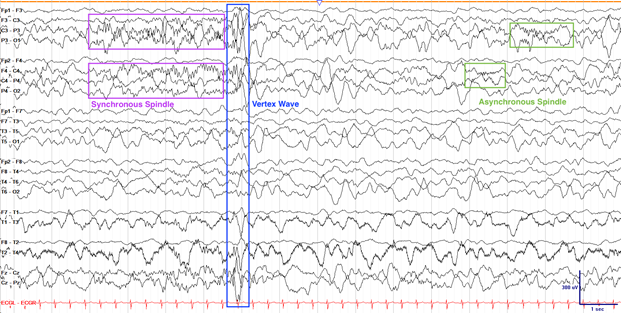

2.关于睡眠

婴儿大约2个月大时开始在睡眠中出现长达15秒的纺锤波,这些波可能在2岁时仍不同步,同时伴随顶点波和K复合波的出现。初生几个月内,婴儿约一半睡眠时间为REM睡眠,这一比例在1至2岁时降至三分之一。

4个月婴儿睡眠纺锤波和高振幅中央波